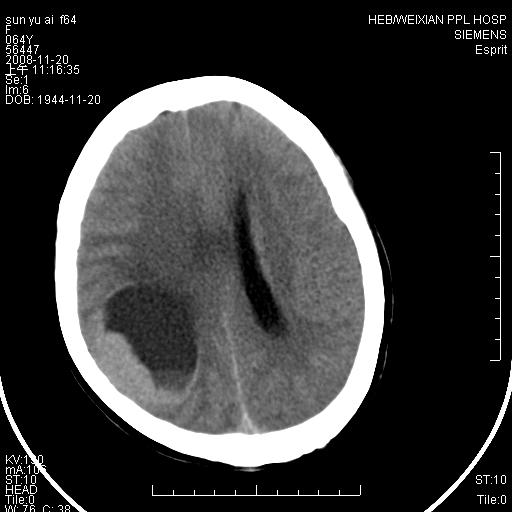

里面还有液平的,多考虑表皮样囊肿,其次考虑胶母及脑膜瘤等,

影像表现:侧脑室三角区附近可见以形态不规则的囊实性肿块,其中以囊性成分为主,实性成分为辅,边缘清晰,未见水肿,轻度占位效应,脉络丛钙化向内上移位,右侧脑室轻度扩大(也许体位所致),

1、右侧大脑半球囊实性占位病变,以囊性变为主,实性部分位于病变外后侧,周围无明显水肿,占位征象明显。

有液平的,多考虑表皮样囊肿,胶质瘤可能?

右颞顶叶囊实性占位,有壁结节。考虑间变性胶质瘤可能性大,建议增强进一步检查。